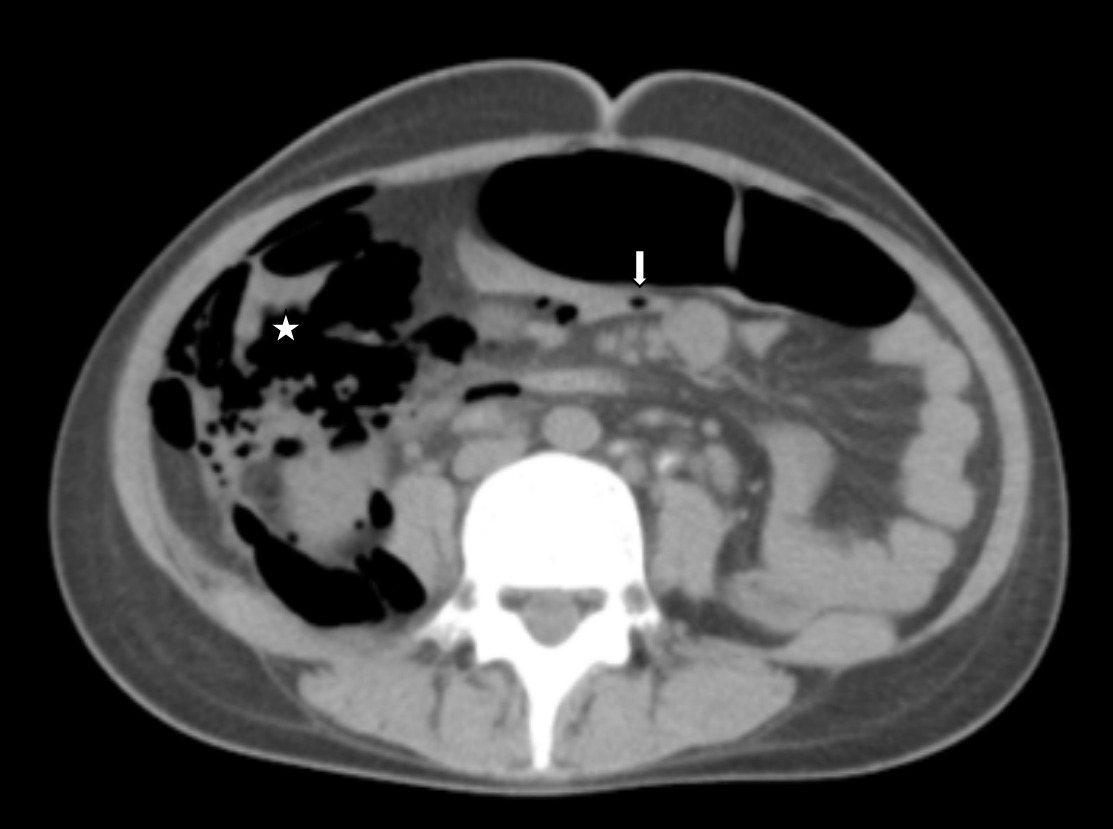

Due to her complaint of mild abdominal discomfort, an abdominal X-ray was ordered. Shortly afterward, she developed shortness of breath and progressive subcutaneous emphysema in the neckThere were no signs of stridor or cyanosis, and her vital signs were stable except for tachycardia. On abdominal examination, the abdomen was soft with normal bowel sounds. Laboratory tests revealed an elevated CRP of 25 mg/L (normal <1 mg/L), a raised total white blood cell count of 13,000/µL (normal 4,000–11,000/µL), low albumin, and hemoglobin at 10 g/dL (normal 11–15 g/dL). All other laboratory parameters were within normal limits, and HIV testing was negative. The abdominal plain radiograph in the anteroposterior (AP) view showed air lucencies centered in the right iliac fossa extending along the right psoas muscle, consistent with pneumo-retroperitoneum(Figure 1A). Clear demarcation of the right renal margin was also noted. Air lucencies further extended along the right suprarenal region and superiorly till the diaphragmatic undersurface in the midline. No air was noted under the bilateral hemidiaphragms, suggestive of the absence of significant intraperitoneal free air. Air was seen extending along the right lateral pre-peritoneal fat plane cranially as well. A plain radiograph of the chest PA view showed extensive soft tissue emphysema along the bilateral sternocleidomastoid muscles as evidenced by air lucencies within (Figure 1B). The soft tissue emphysema was noted to dissect along the fascial planes to involve other neck muscles as well. Pneumomediastinum was also present. A plain radiograph of the neck lateral view revealed the soft tissue emphysema involving the anterior and posterior neck muscles extending cranially to the skull base (Figure 1C).

A plain computed tomography (CT) of the neck, thorax and abdomen was performed. CT axial cuts and soft tissue window of abdomen showed air pockets in the right iliac fossa in relation to the ileo-cecum with pneumo-retroperitoneum and intraperitoneal air in relation to the mesentery (Figure 2). However, air pockets were not present in the subdiaphragmatic region. There were multiple para-aortic and mesenteric lymph nodes, with a few showing calcifications. Pneumomediastinum, bilateral pneumothorax, and subfascial emphysema were also noted. No subdiaphragmatic air pockets were noted in this as well.